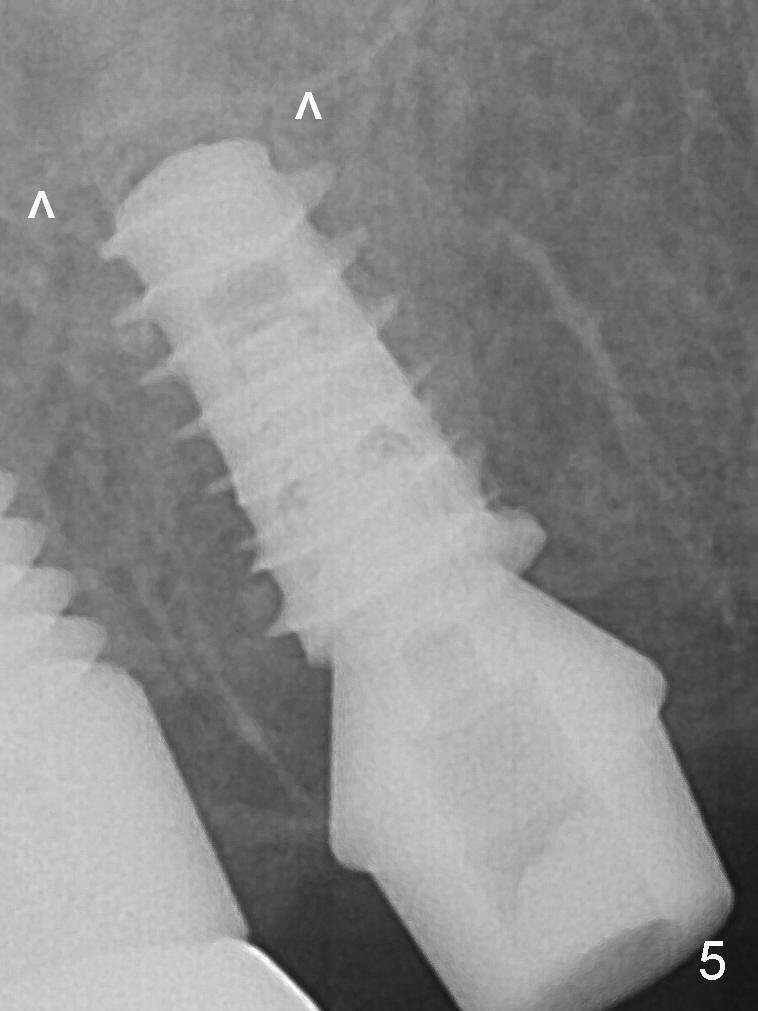

Prior to placement of 5.5x9 mm IBS implant (~ 35 Ncm, Fig.5), a piece of Osteogen plug is inserted into the osteotomy for repair of the perforation. The final implant is also shy of the sinus floor (^). The Osteogen plug is apparently placed underneath the sinus floor so that it should be able to repair hard and soft tissue defects. The remaining sockets are mainly filled with Osteogen plug, while the implant plateau is covered by autogenous bone and Osteogen. A 6.5x4(3) mm abutment is placed for an immediate provisional.